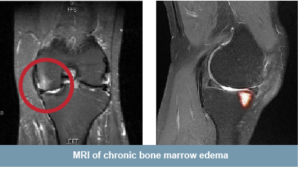

You may have bone defects called Chronic Bone Marrow Lesions (BMLs). BMLs can only be detected via MRI, so only your doctor can tell if you have this condition. Many surgeons believe that chronic BMLs will not heal without treatment such as the Subchondroplasty® procedure.